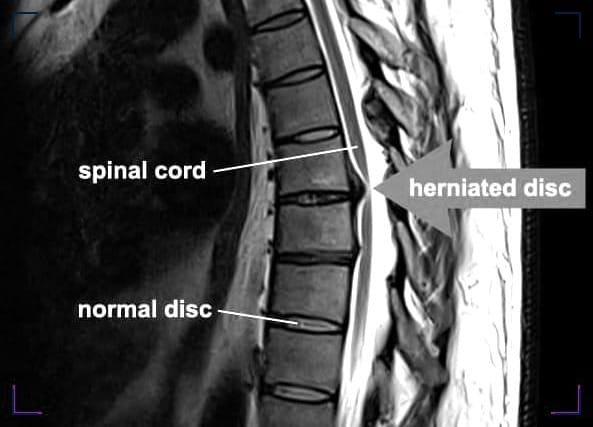

A herniated disc, also known as a slipped or ruptured disc, occurs when the inner gel-like core of a spinal disc pushes out through a tear in the disc's outer ring. This can irritate nearby nerves and result in pain, numbness, or weakness in an arm or leg.

The spine is made up of a series of bones called vertebrae, and between each vertebra is a disc that acts as a cushion and provides flexibility to the spine.

To diagnose a herniated disc, a physician will perform a physical exam and may order imaging tests such as MRI or CT scans to confirm the diagnosis and to rule out other conditions.

An MRI is the most common imaging test used to diagnose a herniated disc in the spine.